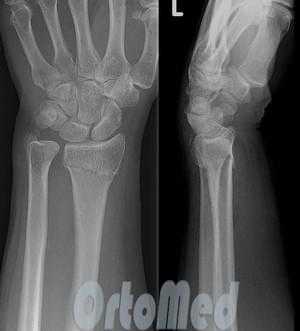

Переломы дистального отдела лучевой кости руки являются наиболее распространенными переломами предплечья и составляет около 16% от всех переломов костей скелета. Как правило, вызваны падением на вытянутую руку. Описание и классификация этих переломов основывается на наличии осколков, линии перелома, смещении отломков, внутрисуставной или внесуставного характера и наличием сопутствующего перелома локтевой кости предплечья.

Рентген анатомия лучезапястного сустава

Наклон суставной поверхности лучевой кости в прямой проекции в норме составляет 15-25º. Измеряется он по отношению перпендикуляра оси лучевой кости и линии вдоль суставной поверхности. Изменение угла наклона суставной поверхности нижней трети лучевой кости является признаком перелома, как свежего так и давно сросшегося.

Ладонный наклон измеряется в боковой проекции по отношению касательной линия проведенной по ладонному и тыльному возвышениям суставной поверхности лучевой кости к осевой линии лучевой кости. Нормальный угол составляет 10-15º. Явное изменение углов является признаком перелома.

Перелом дистального отдела лучевой кости почти всегда происходит около 2-3 см от лучезапястного сустава.

Большинство переломов дистального отдела лучевой диагностируются обычной рентгенографией в 2-х проекциях. Компьютерная томография (КТ) необходима при внутрисуставных переломах.

Для подтверждения диагноза выполняются рентгенограммы лучезапястного сустава в 2-х проекциях. Рентген являются наиболее распространенным и широко доступным диагностическим методом визуализации костей.